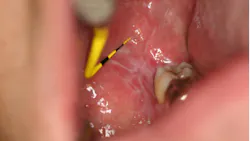

Oral cicatricial pemphigoid

Pemphigoid (figure 12) is a rare autoimmune disease that can affect the oral cavity. It causes ulcerative lesions that can be extremely painful. The cause of pemphigoid is unknown; however, an abnormal response by the body’s immune system resulting in an attack on the oral tissues seems likely. Treatment options to suppress the body’s immune system include topical and systemic corticosteroids and immunosuppressive medications.15